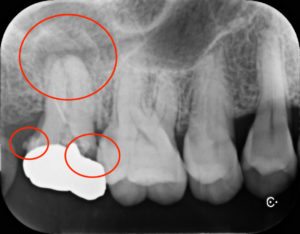

全顎的に診査したところ右上の一番奥の歯に虫歯と根尖病変をみとめました。たまに違和感を感じるとのことで治療を行っていきました。また不適合な補綴物の境目のところに歯石の付着もみとめます。虫歯でほとんど歯質が残っていない状態と考えられますが、再治療を行い歯の保存を行うこととしました。

診断名:上顎右側第二大臼歯 慢性根尖性歯周炎 既根管治療歯および二次う蝕

治療方法:不良補綴物を除去した後、う蝕を除去・隔壁形成した後ラバーダム防湿下にて根管治療を行った。根管内の感染物質を除去した後、通法に従い根管充填した。根尖病変の経過観察を行った後、ジルコニアセラミッククラウンにて歯冠修復を行った。その他全顎的な虫歯治療や歯周治療も行った。

すでに根管治療がされているの歯の再治療例になります。再根管治療の目的は、根管内の感染物質を取り除くことにあります。精度の良いジルコニアセラミッククラウンでの再修復により、根管内に再度感染源が侵入するのを防ぎ、根尖病変の再発を防ぐことで長く歯を使用することが可能となります。